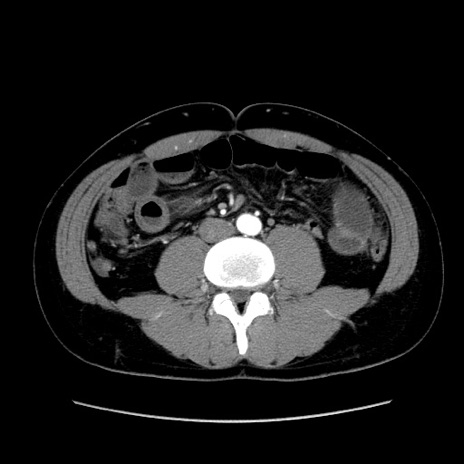

症例36(横断像)

【症例】20歳代 男性

【主訴】心窩部痛

【現病歴】今朝より上腹部痛あり。一旦軽快していたが再度出現したため救急要請。昨日夕に白身の魚を含む刺身を食べた。

【身体所見】BP 136/89mmHg、HR 74/min、BT 37.0℃、腹部:膨満、軟、心窩部に圧痛あり。反跳痛なし、筋性防御なし、腸雑音やや亢進あり。

【データ】WBC 17700、CRP 0.48